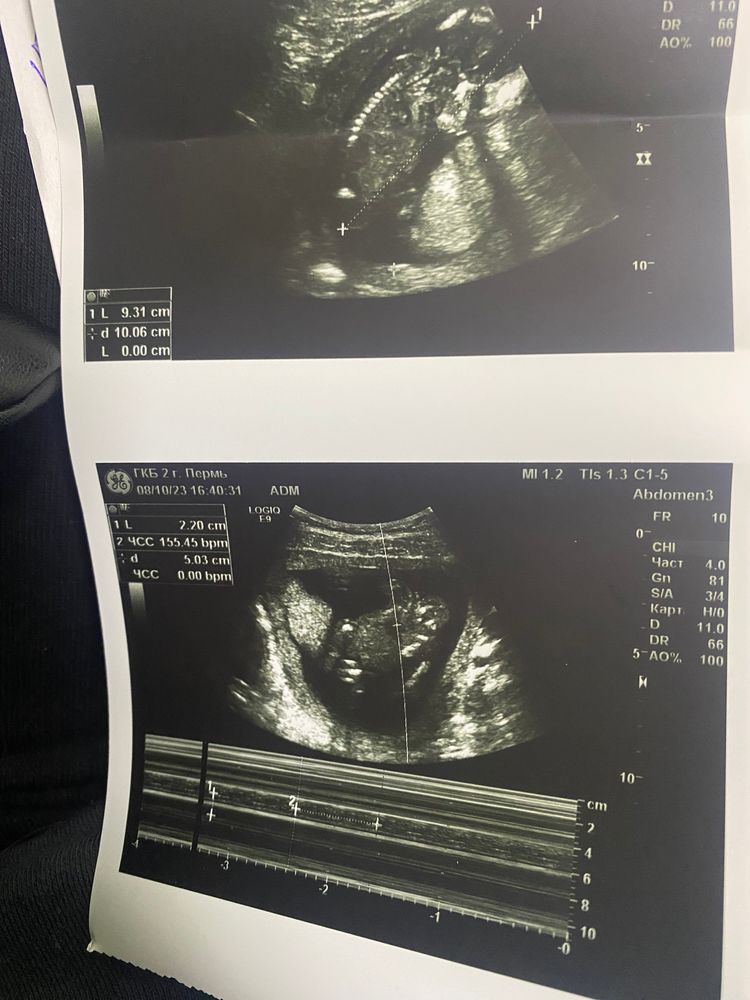

Узи 15 недель

Она увидела пол, но я попросила не говорить, а потом в результатах узи увидела фоточку

фото в комментариях

Единственное меня смутило КТР 83 мм🫤, скажите, норма ли? По 1 скринингу у меня было +3 дня